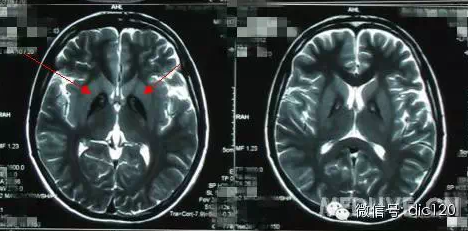

診斷小腦萎縮通常需要進行神經系統檢查、影像學檢查(如腦部CT或MRI)和實驗室測試,治療小腦萎縮的方法主要包括藥物治療、物理治療和康復訓練等,藥物治療旨在緩解癥狀和改善生活質量,物理治療幫助患者恢復肌肉力量和運動功能,康復訓練則包括語言治療、認知訓練和心理支持等。